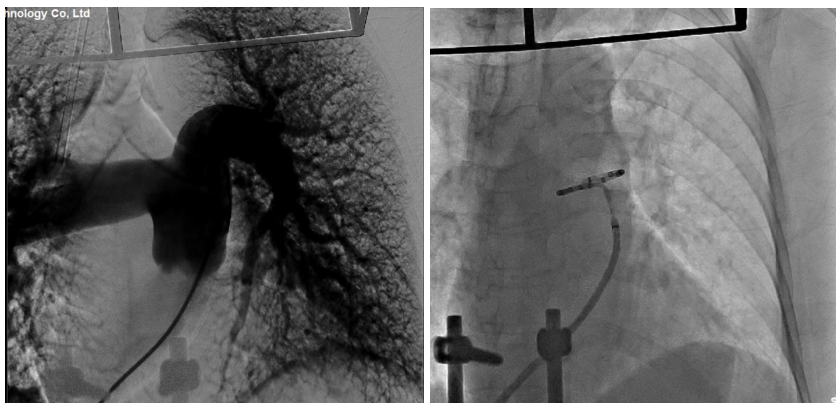

心血管病院特聘专家南京医科大学附属南京医院陈绍良教授团队讨论后,决定为该患者采取该领域前沿的介入治疗手段——经皮肺动脉去神经术(PADN)。在完成了充分、周全的术前准备工作后,吴皓宇副主任团队成功应用了我国原创的PADN肺动脉射频消融导管,对患者肺动脉交感神经消融靶点进行“点对点”精准消融。整个手术过程患者无明显不适,术中各监测指标平稳。右心导管检查显示,患者肺动脉收缩压由术前的91mmHg降至术后即刻的72mmHg,预期中远期肺动脉压力将进一步改善。